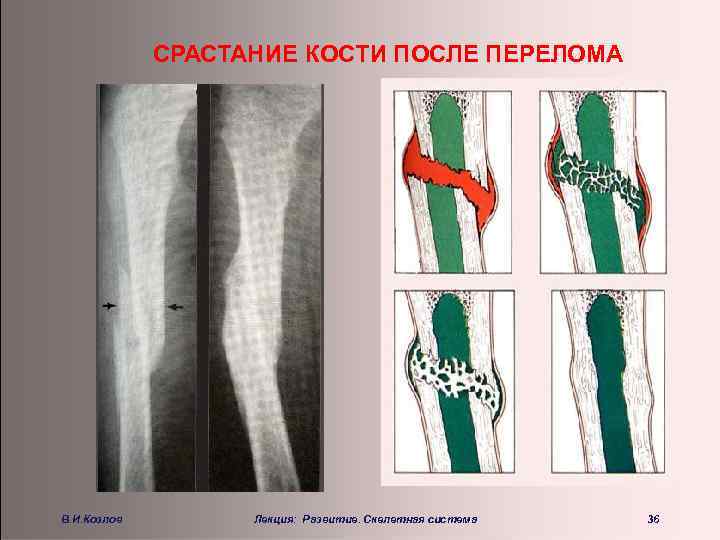

СРАСТАНИЕ КОСТИ ПОСЛЕ ПЕРЕЛОМА В. И. Козлов Лекция: Развитие. Скелетная система 36